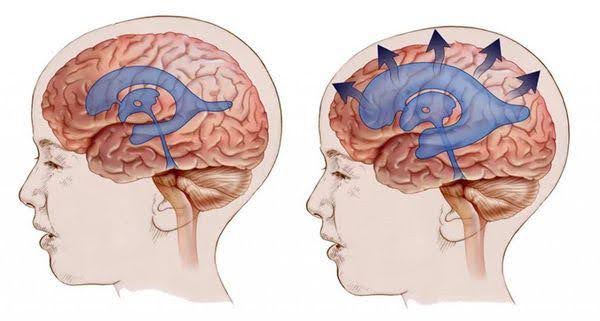

Hidrocefalia: Entendiendo el Diagnóstico y Tratamiento

La hidrocefalia es una condición que ocurre cuando hay una acumulación anormal de líquido cefalorra...